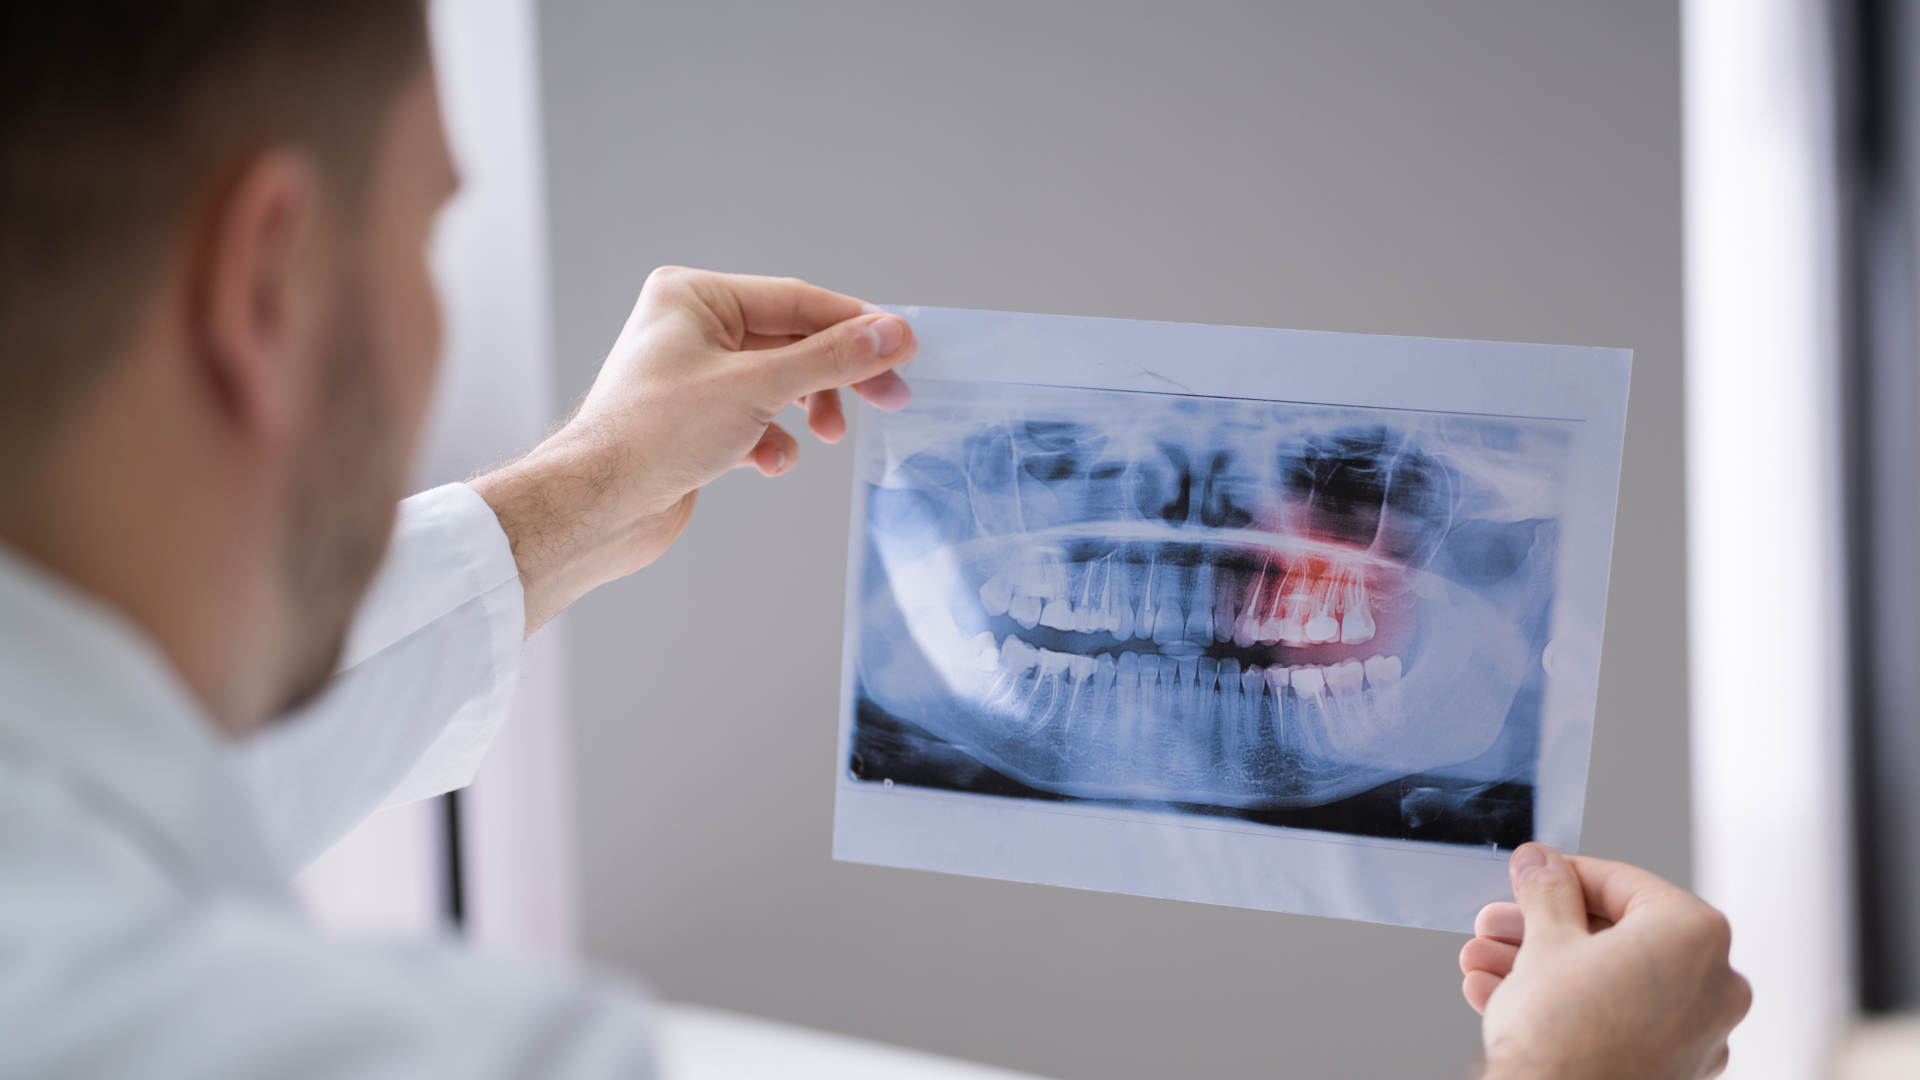

Vì vậy, chẩn đoán hình ảnh qua phim X-quang là bước bắt buộc để phân biệt chính xác các tình trạng này.

Khi đến khám với nghi ngờ có hay không tình trạng mọc 5 răng khôn, người bệnh sẽ được bác sĩ thăm khám lâm sàng trực tiếp để đánh giá tình trạng nướu và cung hàm. Bước tiếp theo là chụp X-quang toàn hàm hoặc phim cắt lớp nếu cần để xác định chính xác số lượng, vị trí và hướng mọc của tất cả các răng trong xương hàm. Dựa trên kết quả, bác sĩ sẽ tư vấn kế hoạch theo dõi hoặc can thiệp phù hợp với từng trường hợp cụ thể.